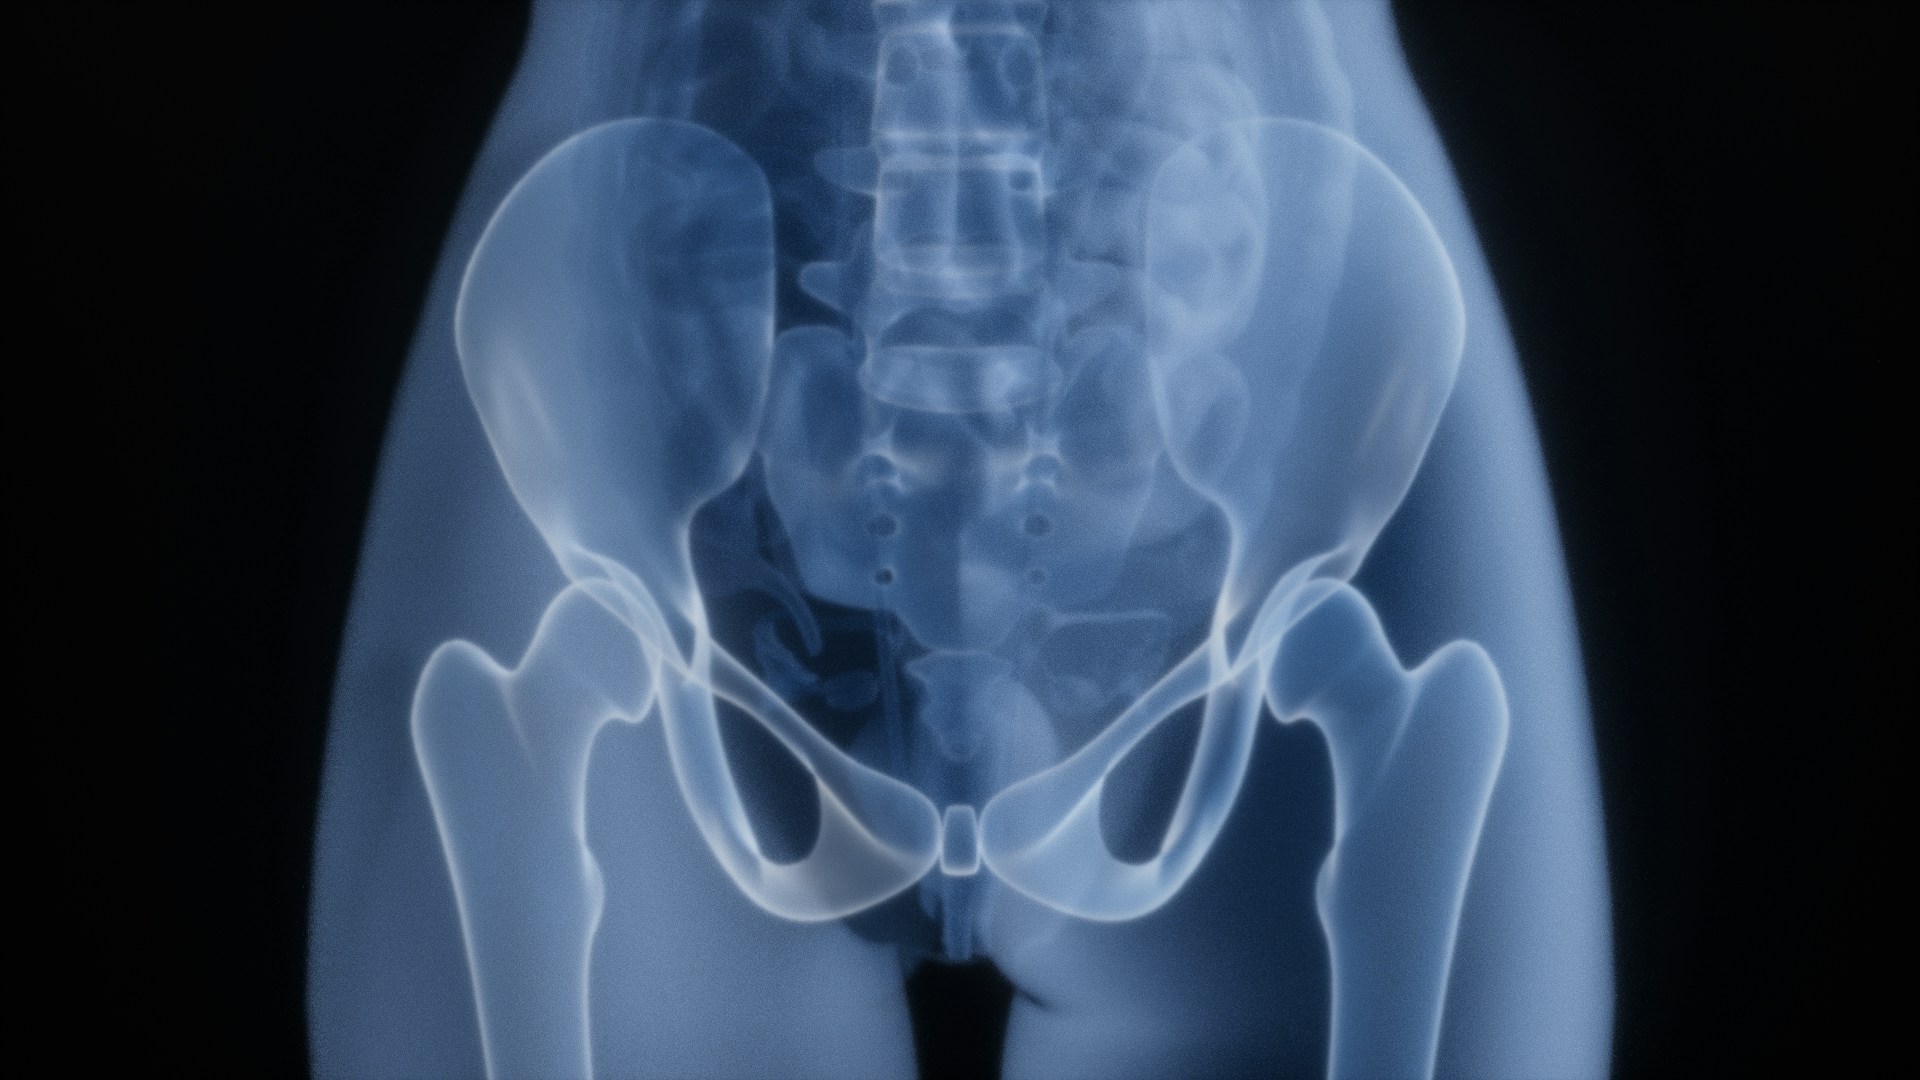

お尻から摘出された変なモノランキング2025年版が発表される

1位 野球ボール

2位 バッテリー式ライト

3位 髭トリマー

その他は以下参照